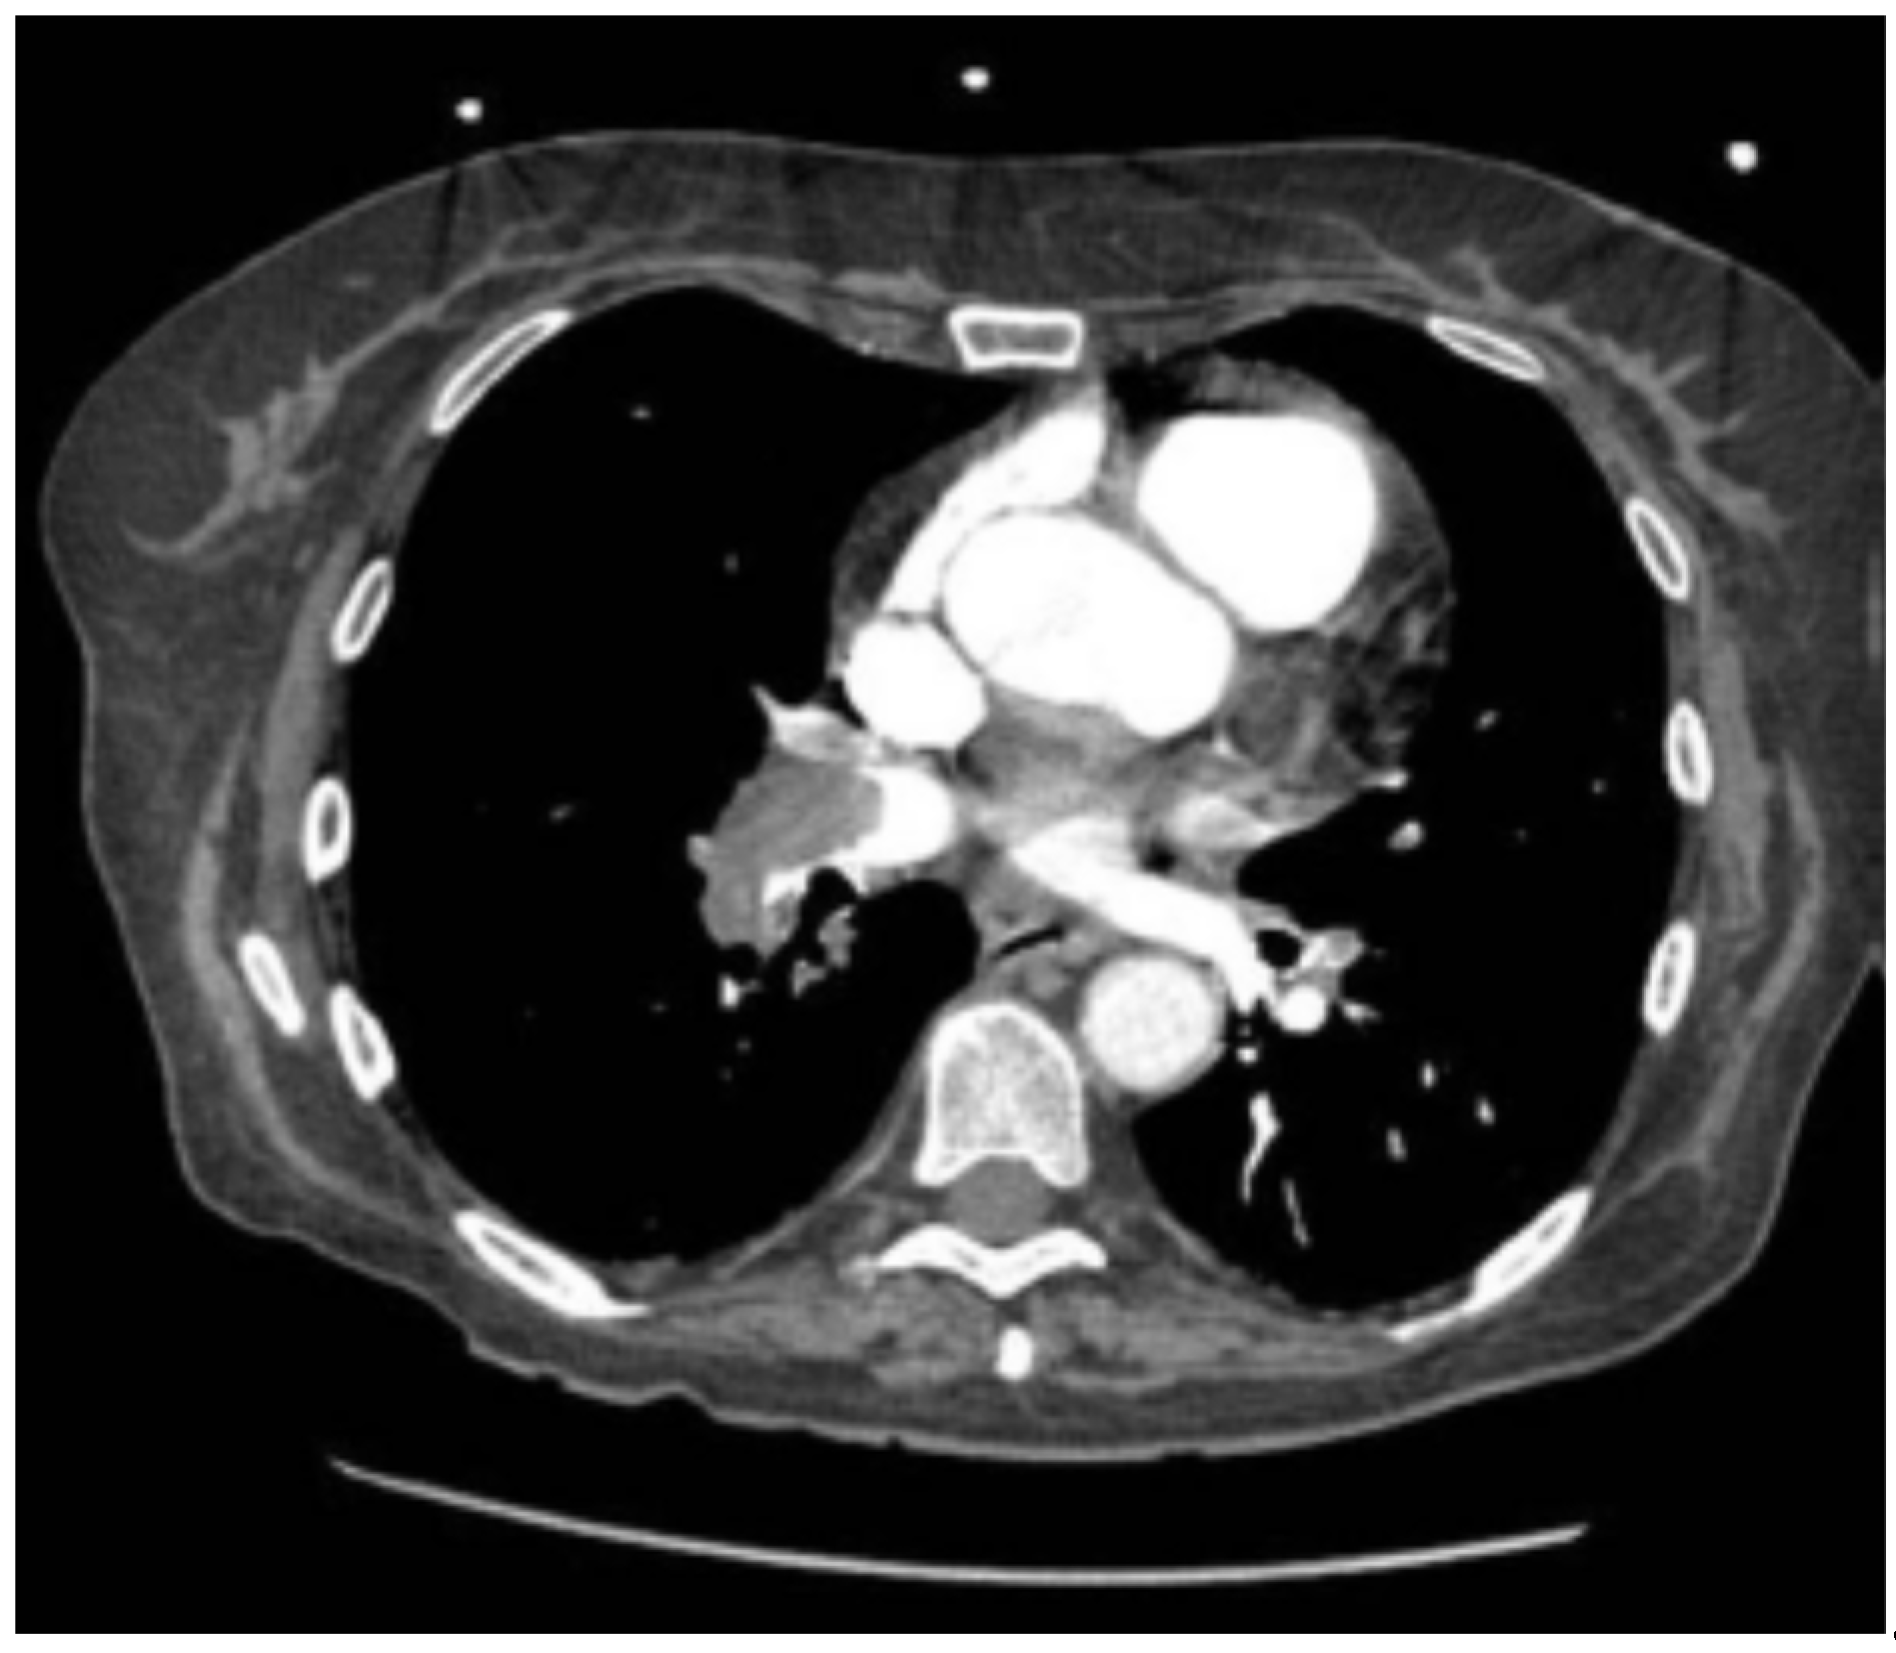

Thoracic CT angiography revealed massive bilateral pulmonary embolism with right chamber involvement and signs of right heart failure. (Figure 1)

Figure 1. CT angiography showing bilateral proximal PE and RV dilation.